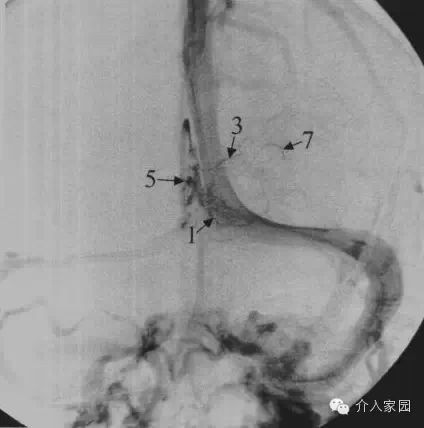

1、丘紋靜脈 2、透明隔靜脈 3、基底靜脈 4、海綿竇 5、頸內靜脈 6、上矢狀竇

7、下矢狀竇 8、大腦內靜脈 9、大腦大靜脈 10、直竇 11、竇彙 12、橫竇

13、乙狀竇